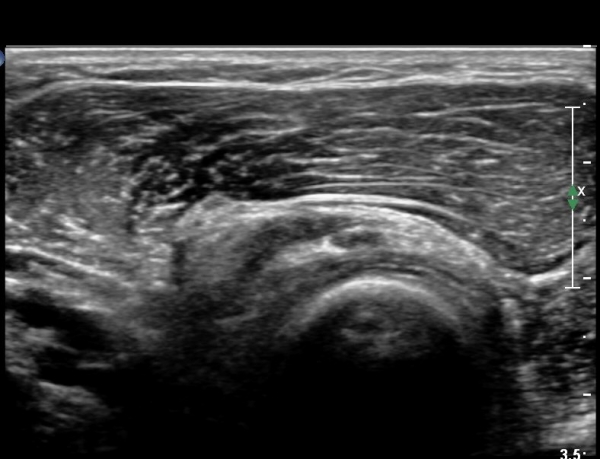

ŽÃÊÀÚ¸¦ ȸ¿Ü±Ù ºÎÀ§±îÁö À̵¿ÇÏ´Ï ³¶Á¾Àº °í³ªÂûµÇÁö ¾Ê°í µÎ ȸ¿Ü±Ù »çÀÌ¿¡ Àִ  Èİñ°£½Å°æ

ºÎÁ¾ÀÌ °üÂûµÈ´Ù(»çÁø 4).

Èİñ°£½Å°æ Á¾´Ü¸é°Ë»ç¿¡¼­ ³¶Á¾°ú ÀÎÁ¢ÇÏ¿©  À§Ä¡ÇÑ Èİñ°£½Å°æÀÇ ºÎÁ¾ÀÌ °üÂûµÈ´Ù(»çÁø 5, 6).